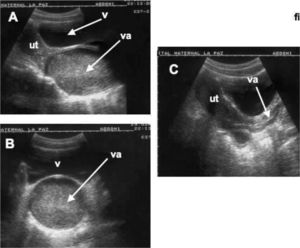

MALFORMACIONES CONGÉNITAS DEL APARATO GENITALHimen imperforado-hematocolposEste proceso aparece entre niñas de 11 y 14 años, después de la pubertad asociado a una que amenorrea primaria. El flujo menstrual se va acumulando progresivamente distendiendo la vagina y dando lugar a un hematocolpos (fig. 2). El diagnóstico ecográfico evidencia una formación quística alargada o tubular por debajo del útero y de la vagina que presenta un contenido puntiforme más o menos homogéneo en dependencia de los fenómenos de coagulación que tengan lugar en el sangrado menstrual. Esta imagen y los síntomas clínicos asociados ayudan a hacer el diagnóstico. La apertura quirúrgica del himen y la consiguiente salida de la sangre menstrual devuelven la típica silueta ecográfica de la vagina y el útero. En algunas ocasiones, también se produce, y por el mismo motivo, una distensión de la propia cavidad endometrial (hematometra).

Himen imperforado. Hematocolpos. A) Corte sagital del aparato genital de una niña de 13 años. En primer término, a la izquierda, se observa el útero (Ut) y a la derecha la vejiga (V). En el centro se aprecia la vagina (va) abultada y distendida con un contenido líquido denso y puntiforme (sangre menstrual). B) Corte transversal de la vagina distendida (va) por debajo de la vejiga (V). C) Imagen ecográfica sagital posterior a la perforación quirúrgica del himen en la que se aprecia un útero y vagina normales.